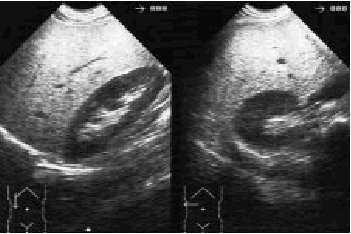

El diagnóstico suele hacerse mediante la ultrasonografía abdominal, técnica que por su gran accesibilidad y bajo coste es el método de imagen que más se suele usar en la medicina primaria. Es muy característico que la ecogenicidad del parénquima hepático en estos casos sea homogénea, y esté aumentada, habitualmente de forma difusa, por lo que se observa de esta manera un hígado «brillante» (fig. 1). En lo que respecta al tratamiento se debe aconsejar una disminución gradual del peso, sabiendo que una pérdida del 10% del peso suele restaurar los datos analíticos a valores normales y que por cada 1% de peso perdido la GPT puede disminuir cerca de un 10%.

Fig. 1. Ecografía abdominal (corte longitudinal y transversal) en la que se observa la imagen característica de una esteatosis hepática.